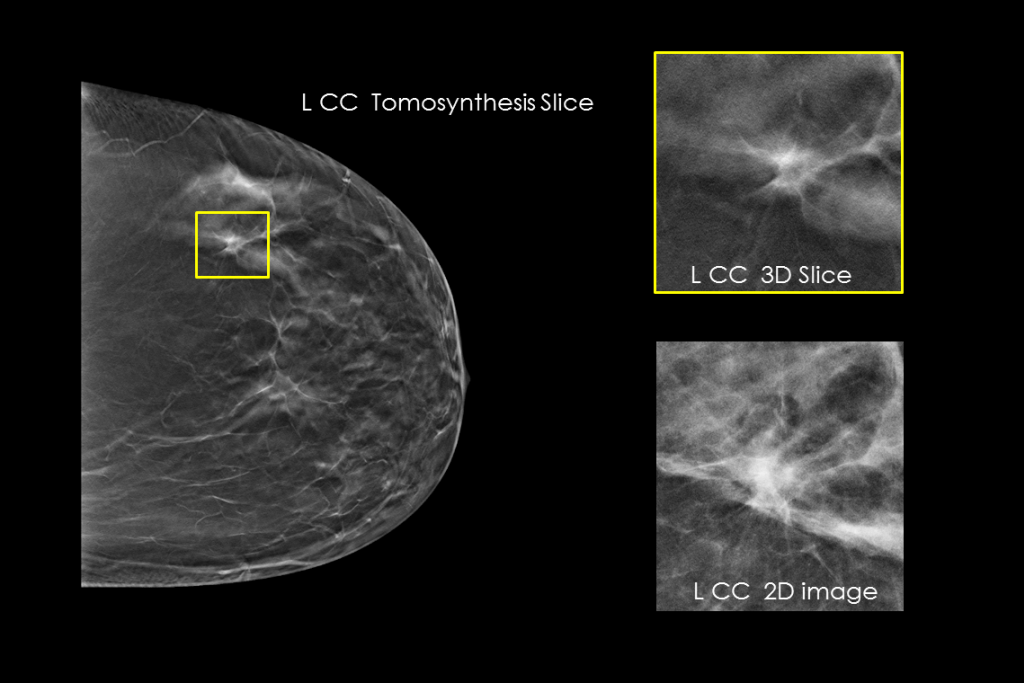

Kliniske billeder fra mammografi af et bryst

Kliniske billeder fra mammografi af et bryst med en mistænkelig læsion